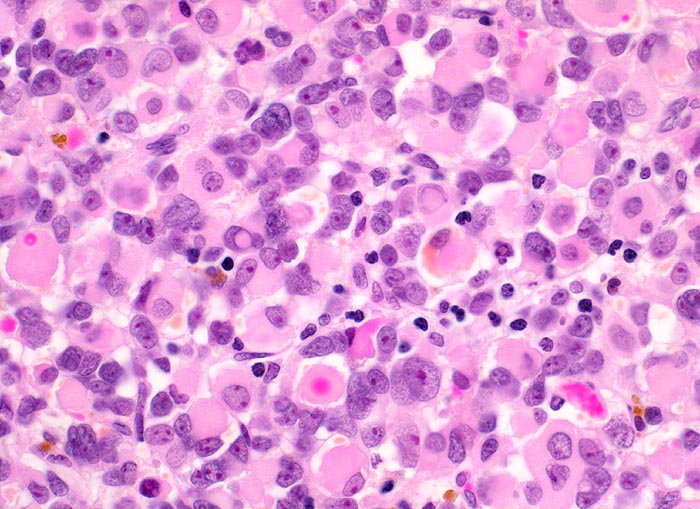

• Konjunktivalschleimhautfragment. Fibrinauflagerungen anstelle der langstreckig abgeschilferten konjunktivalen Zylinderepithelbedeckung (unten).

• Chronisches lymphoplasmazelluläres Entzündungsinfiltrat im subepithelialen Stroma mit unscharfer Begrenzung zu einem zellreichen soliden Tumor.

• Dieser besteht aus mesenchymalen Zellen mit unterschiedlicher Ausdifferenzierung.

• Die am wenigsten ausdifferenzierten Zellen zeigen wenig amphophiles Zytoplasma und ovale Kerne.

• Dominierend sind in diesem Tumor teils mehrkernige Rhabdomyoblasten mit reichlich eosinophilem Zytoplasma und exzentrischem Zellkern. Die Querstreifung des Zytoplasmas ist in der HE Färbung nur andeutungsweise erkennbar.

• "Spinnwebenzellen" mit peripheren Zytoplasmavakuolen.